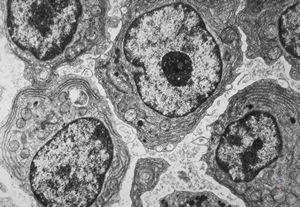

F,51y. | blood - chronic lymphatic leukemia … prolymphocyte

F,72y. | blood - lymphoplasmocellular leukemia

F,61y. | blood - lymphoplasmocellular leukemia